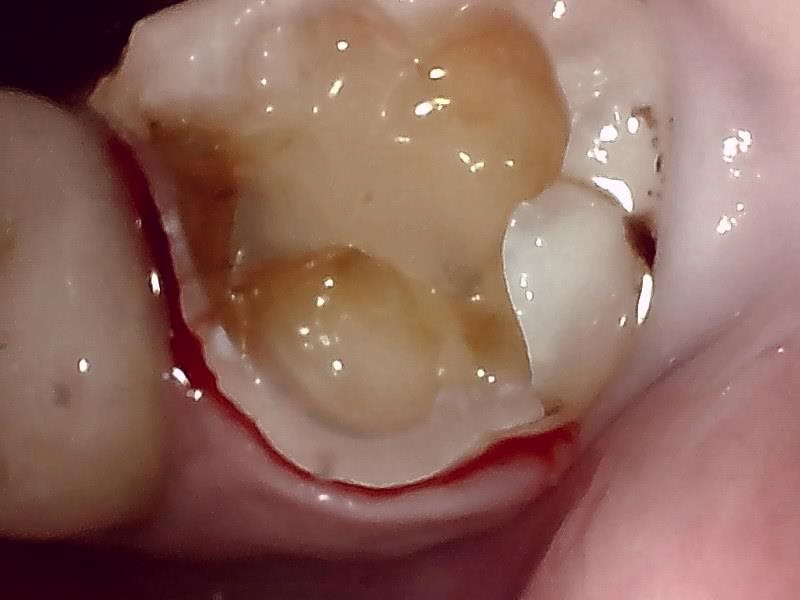

| 治療方針 | セラミックインレーの周りが2次的な虫歯になっているので、新たにジルコニアインレーでつめ直しました。 |

| 特記事項 | 2016年にセラミックインレーで治療した歯です。歯の遠心(一番奥側)のキワが黒くむし歯になっていたのと、噛む面のつめ物と歯の境目に穴が空いてきていたので、インレーをやり直すことになりました。 |

| 担当者所見 | 検診で毎回チェックしていた箇所です。 今回の検診で以前よりも虫歯が大きくなってきていたのでやり直しました。 つめ物で直して終わりではなく、その後のケアも大切ということをお伝えしました。 |